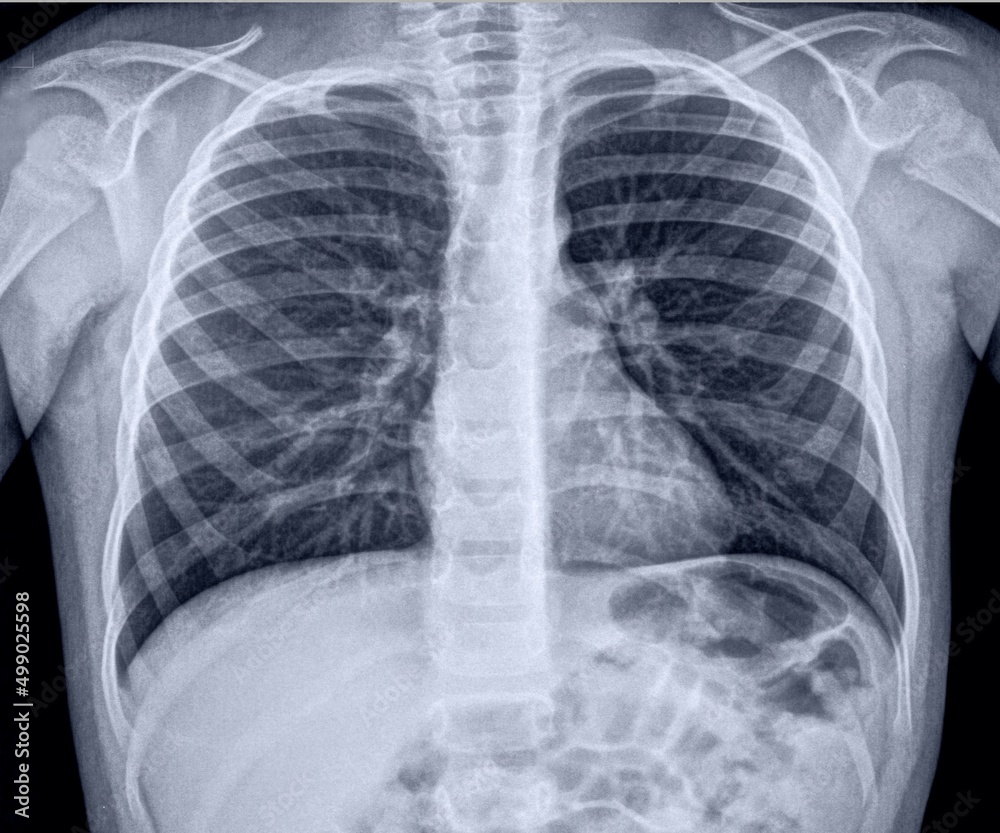

Chest X‐ray Bilateral pneumonia and large right pleural effusion Download Scientific Diagram Chest X Ray Pneumonia Pleural Effusion Pleural effusion associated with congestive heart failure patients with congestive heart failure and pleural effusion present with. Pleural effusion can easily be detected by conventional. Parapneumonic effusions refer to an exudative pleural effusion associated with pneumonia. Dullness to percussion on physical examination suggests an effusion; Chest radiography can confirm the diagnosis. Chest X Ray Pneumonia Pleural Effusion.

Bilateral Pleural Effusion Chest X Ray Pleural Effusion Concise Medical Knowledge / Bilateral Chest X Ray Pneumonia Pleural Effusion Pleural effusion associated with congestive heart failure patients with congestive heart failure and pleural effusion present with. Pleural effusion can easily be detected by conventional. Parapneumonic effusions refer to an exudative pleural effusion associated with pneumonia. Chest radiography can confirm the diagnosis. Dullness to percussion on physical examination suggests an effusion; Chest X Ray Pneumonia Pleural Effusion.

Bilateral Pleural Effusion Chest X Ray Pleural Effusion Concise Medical Knowledge / Bilateral Chest X Ray Pneumonia Pleural Effusion Pleural effusion associated with congestive heart failure patients with congestive heart failure and pleural effusion present with. Parapneumonic effusions refer to an exudative pleural effusion associated with pneumonia. Dullness to percussion on physical examination suggests an effusion; Pleural effusion can easily be detected by conventional. Chest radiography can confirm the diagnosis. Chest X Ray Pneumonia Pleural Effusion.